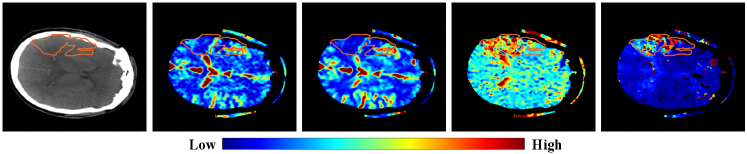

The 2018 ISLES challenge is the first to use CTP data. Currently, MR with diffusion-weighted imaging (DWI) is considered the most accurate and earliest at detecting acute stroke [9, 1]. CTP however is advantageous in cost, speed, and availability in acute care units [9]. Furthermore, CTP is emerging as an effective means to detect the infarct (irreversible) core with high sensitivity and specificity [9, 1]. Detection relies on quantitative evaluation metrics derived from the CTP data. For example, a drop in cerebral blood flow (CBF) is a result of an occlusion of blood supply [3]. In this work, we use the CT image, CBF, cerebral blood volume (CBV), time to peak (TTP) and mean transit time (MTT) of the contrast agent injection as signals to identify the infarct core.

Fully convolutional neural network architectures were trained to predict ischemic stroke lesion masks. We constructed both 2D and 3D CNN models, but found stronger performance in 2D per-slice models given the variable and limited number of axial slices in the scans. The input to the network was a multi-channel 2D image created by stacking a CT slice together with its four corresponding perfusion map slices (Tmax, CBF, CBV, MTT). Cross entropy and focal loss [14] were evaluated as loss functions. We developed models based on the pyramid scene parsing network (PSPNet), [27], the U-Net (2D and 3D) [22, 7], and the 3D V-Net [18] architectures. Our final model is based on the PSPNet with focal loss. The PSPNet employs pyramid pooling (explained below) within a fully convolutional neural network.